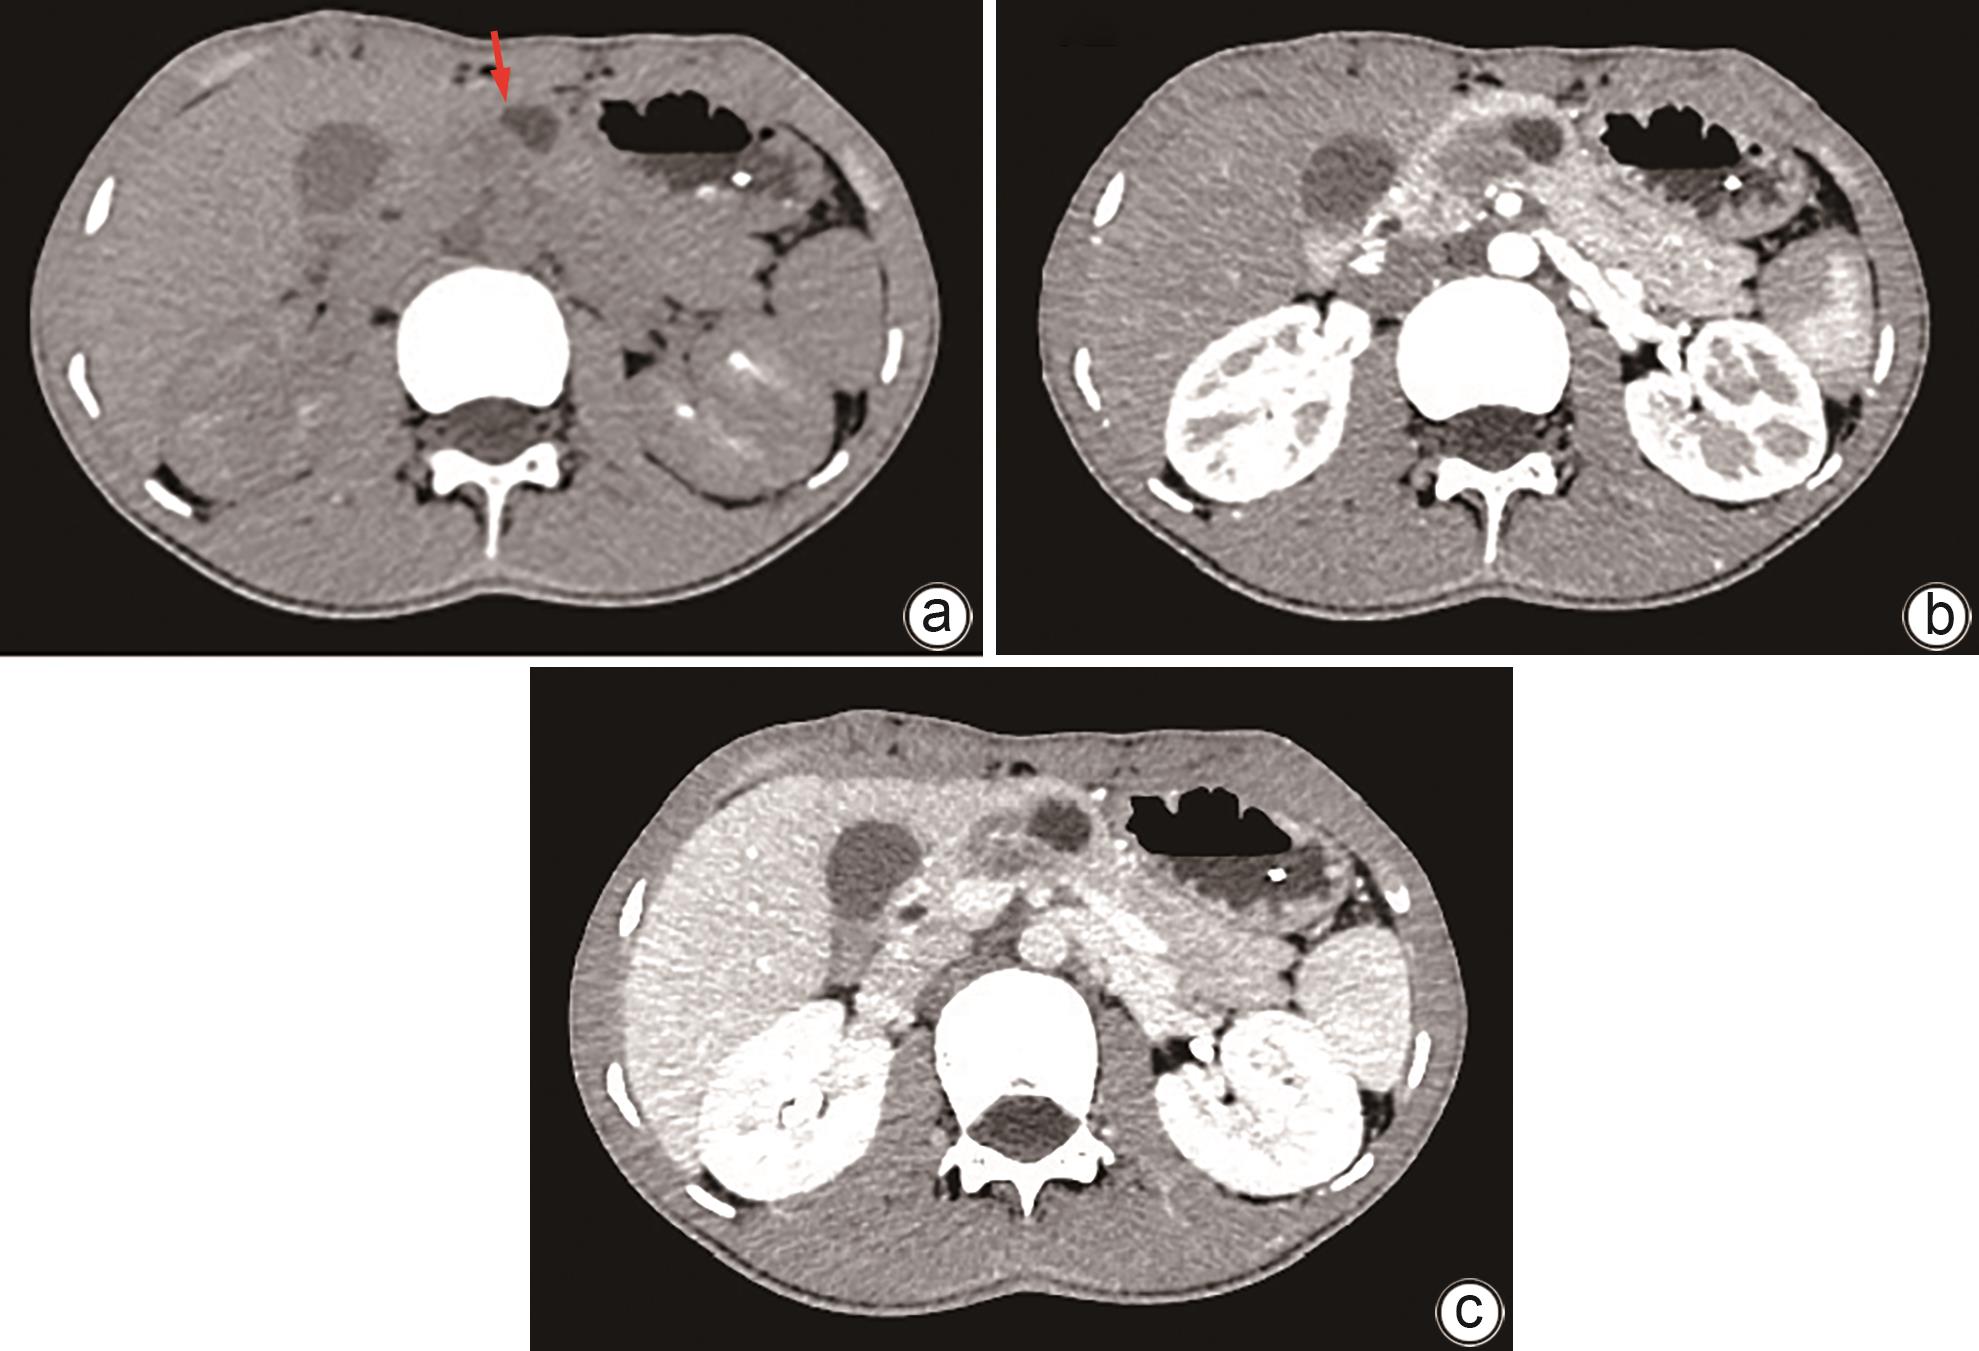

Imaging features and therapeutic strategies for lethal iatrogenic hemobilia

Chen WANG, Min WANG, Ke ZHANG, Jinxing ZHANG, Li LIU, Zhining FAN

2024, 40(10): 2070-2074. DOI: 10.12449/JCH241022

Abstract(1032) HTML (357) PDF (2026KB)(84)

Abstract:

Objective  To investigate the imaging features and pathogenesis of lethal iatrogenic hemobilia (LIH) and the value of transarterial intervention in the treatment of LIH.  Methods  A total of 269 patients with upper gastrointestinal bleeding who were admitted to The First Affiliated Hospital of Nanjing Medical University from August 2009 to July 2023 were enrolled, among whom 24 had a confirmed diagnosis of LIH and received treatment, and a retrospective analysis was performed for the clinical data of these 24 patients, including the iatrogenic causes, angiographic findings, and arterial interventions of LIH. Among the 24 patients, 23 received transarterial embolization (TAE) with gelatin sponge particles and coils, and 1 received a covered stent for isolation. The main criteria for assessing treatment outcome included the technical success rate of surgery, procedure-related complications, and long-term clinical follow-up.  Results  Among the 24 patients with LIH, 12 had LIH caused by interventional procedures, and 12 had LIH caused by hepatobiliary and pancreatic surgery. The main clinical manifestations included a significant reduction in blood pressure or a persistent reduction in hemoglobin in 13 patients and upper gastrointestinal bleeding in 18 patients. Among the 24 patients, 2 developed symptoms during surgery, 4 developed symptoms within 24 hours, and 18 developed symptoms after 24 hours. Angiography showed a positive bleeding rate of 100% (24/24), and imaging findings included pseudoaneurysms in 15 patients, hepatic artery truncation in 3 patients, extravasation of contrast medium in 5 patients, and hepatic arteriobiliary fistula in 3 patients. Among the 24 patients, 23 received TAE and 1 received stent implantation. Successful hemostasis was achieved for 23 patients, with a technical success rate of 95.8% (23/24). Four patients developed hepatic necrosis and abscess after TAE, and there was no rebleeding or recurrence after hemostatic treatment.  Conclusion  Various iatrogenic injuries may result in LIH with diverse clinical and imaging findings, and integrated diagnostic imaging combined with transarterial intervention is the best effective life-saving measure for LIH.